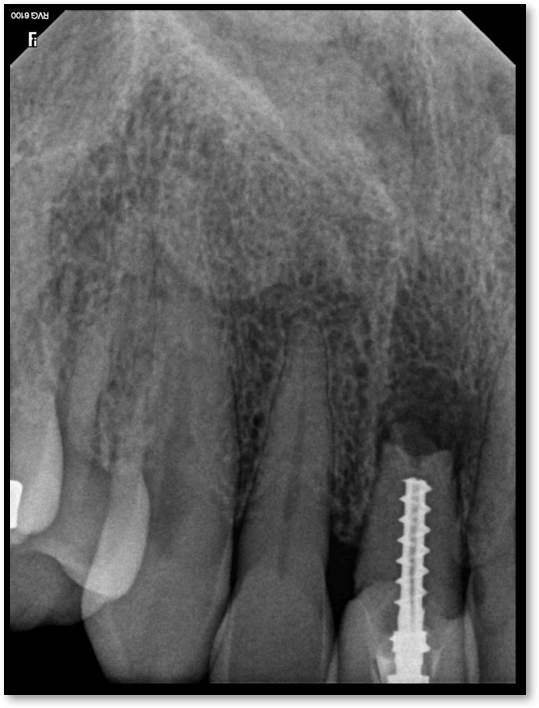

Fig 17. A case with a good fiber post on the lateral that could be longer.

Figure 17